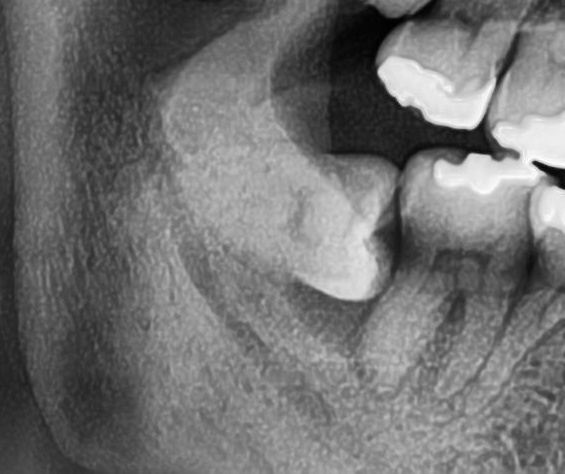

次にパノラマ写真を撮影してみると、右下の親知らずは、手前の歯の根っこを押すように横向きに生えているのが確認できました。